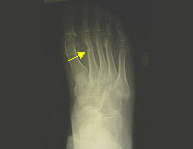

The foot region is a set of bones and joints with many features among which support our weight and ambulation (walking). The foot in turn is divided into three parts: the hindfoot, midfoot and forefoot. Every region suffers from its peculiar injuries. In sport foot injuries are common due to the involvement of it in most of them. Usually foot fractures respond well to conservative treatment reserving the surgical approach to those complex irreparable injuries in the hindfoot.